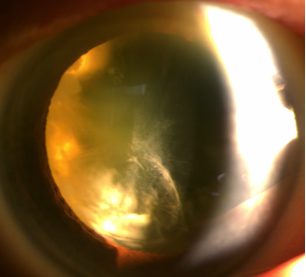

모 대학병원의 의뢰로 내원하신 70대 환자분인데요.

눈 상태가 전반적으로 매우 심각했습니다.

먼저 시력은 우안은 안전수지였고,

(손가락 개수 정도만 겨우 파악할 수 있는 시력, 0.02 미만)

좌안도 0.1을 제대로 읽지 못하는 상태,

안경을 착용해도 시력이 전혀 교정되지 않았죠.

게다가 우안에는 다음과 같은 3가지 심각한 문제가 발견되었습니다.

1) 과숙백내장(오래 방치된 심한 백내장)

2) 거짓비늘증후군

3) 망막박리

초고도근시와 녹내장까지 있어서 상황은 더욱 복잡했죠.